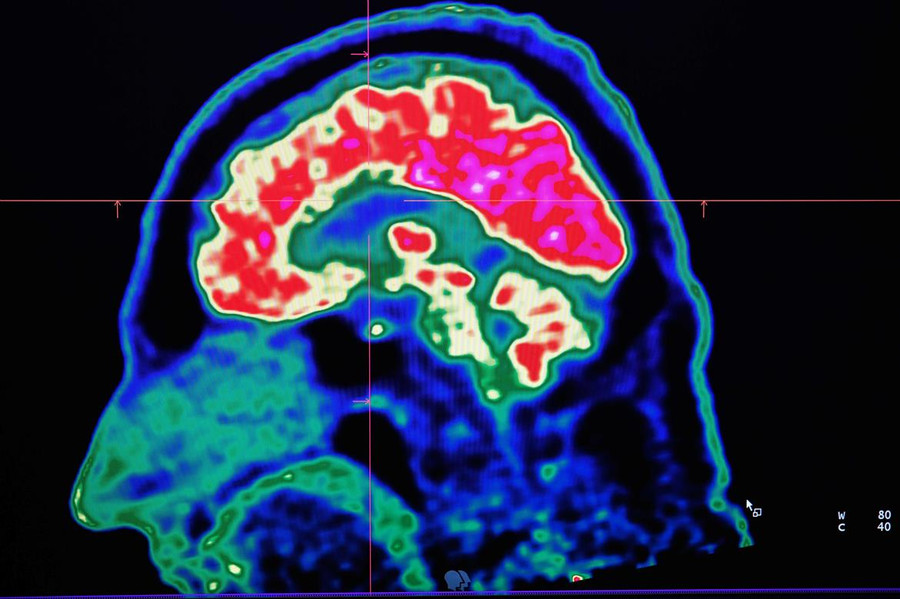

Hình ảnh y học hạt nhân (PET)

Trong lĩnh vực y học hạt nhân, bác sĩ thường được hỏi: nếu như chụp hình ảnh y học hạt nhân có còn phù hợp khi chúng ta đang có những phương pháp hình ảnh tốt khác?

Câu trả lời rất đơn giản: Chụp hình ảnh y học hạt nhân có thế mạnh về chụp hình ảnh chức năng. Trong hình ảnh y học hạt nhân, một lượng nhỏ chất phóng xạ được sử dụng độc lập hay kết hợp với các dược phẩm đặc biệt nhằm trực quan hóa cơ quan nội tạng muốn quan tâm.

Hình ảnh PET hiện tại là một phương pháp được xem là tiên tiến trong quản lý bệnh ung thư. Cho dù dùng CT hay MRI (PET/CT hay PET/MRI), nhưng độ nhạy cao trong phát hiện các căn bệnh ung thư và xác định mức độ của hoạt động trao đổi chất trong ung thư là rất hữu dụng cho các bác sĩ lâm sàng.